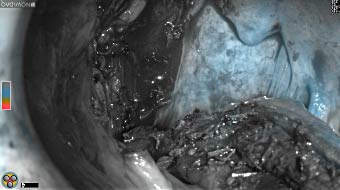

Intraoperative imaging panitumumab-IRDye800 (fluorescence)

Primary tumor prior to resection

Wound bed post re-resection of tumor

Fluorescence imaging of the tumor was performed prior to resection and after resection to “check” the wound bed. In the upper row the tumor is clearly visible with fluorescence and in the bottom row you can see that the wound bed is empty – there is no suspicious fluorescence left. The middle column of tiles show the fluorescence signal in black and white where the “white” represents the tumor and the black the background (= no fluorescence signal). The right column of tiles shows the overlay of the brightfield photo (in greyscale) and the fluorescence (red-yellow-blue heatmap). This image provides anatomical context to the surgeon – the surgeon can see where is the fluorescence located with regard to the tumor area.